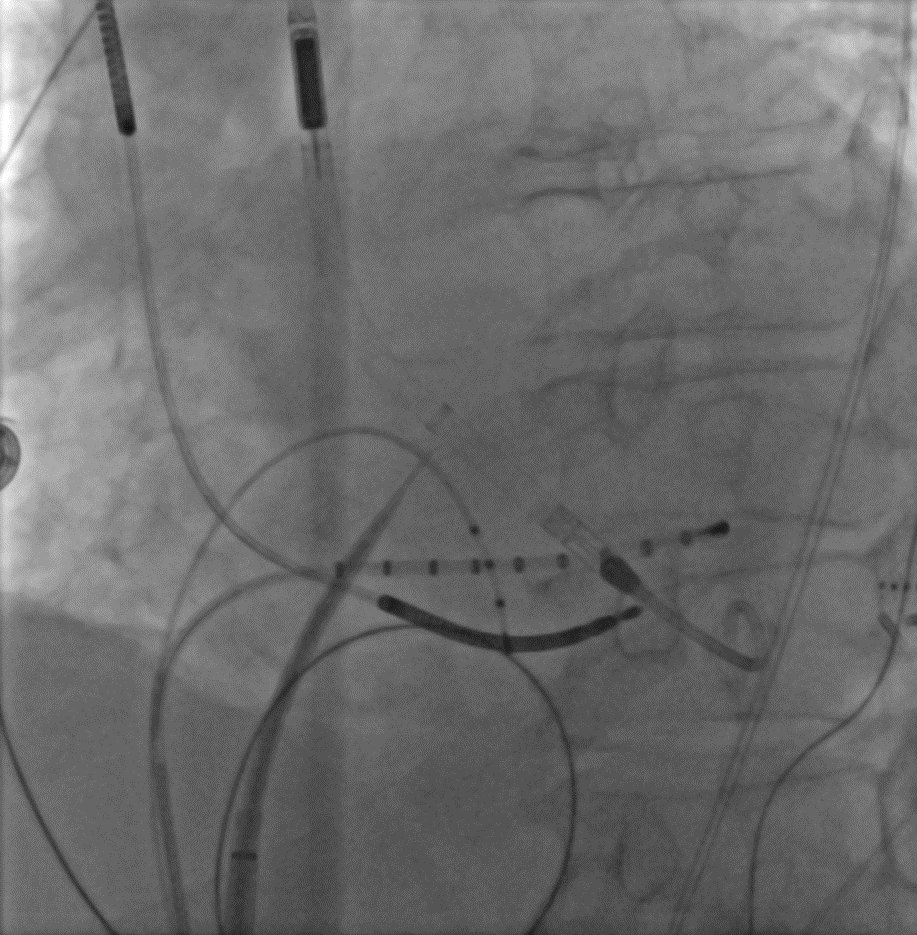

Ablation von Kammertachykardie mit Herzpumpe

Für die Untersuchung benötigt man neben dem Ablationskatheter drei diagnostische Elektrodenkatheter. Diese werden über die Leistenvenen bis zum Herzen eingeführt. Deshalb werden beide Leisten für diese Untersuchung vorbereitet. Falls eine Herzpumpe notwendig ist, wird diese in der Regel über die linke Oberschenkelarterie bis in die linke Herzkammer gelegt. Die Behandlung wird unter lokaler Betäubung und intravenöser Schmerz- und Sedierungstherapie durchgeführt.

Falls es doch unter der Rhythmusstörung zu einer hämodynamischen Instabilität kommt, dann kommen spezielle Herzpumpen zum Einsatz. Mithilfe dieser Herzpumpen kann der Blutdruck trotz der sehr schnellen Rhythmusstörung aufrechterhalten werden (siehe Abbildung 2).